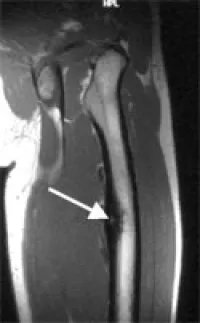

Imaging usually is very typical: X-rays show new bone formation and sometimes a small lucent spot (smaller than 1.5 cm), which is defined as the nidus. Computed tomography (cat scan, CT) is even better suited to show the new bone formation and the nidus. Because there may be a lot of inflammatory swelling and edema in the bone and soft tissues around the tumor magnetic resonance imaging (MRI) may sometimes be difficult to interpret and CT may be required to further assess these tumors. Radionuclide or bone scans show increased uptake of the radioactive tracer, this may sometimes be very focal.

Magnetic resonance image of an osteoid osteoma of the thigh (femur). Increased bone formation (dark) surrounding a brighter spot representing the nidus (arrow) of the osteoid osteoma.